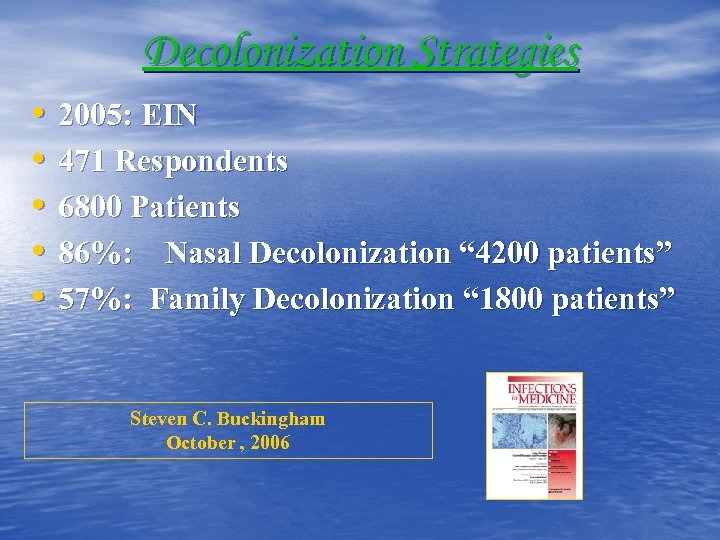

Decolonization Strategies • • • 2005: EIN 471 Respondents 6800 Patients 86%: Nasal Decolonization “ 4200 patients” 57%: Family Decolonization “ 1800 patients” Steven C. Buckingham October , 2006

Decolonization Strategies • • • 2005: EIN 471 Respondents 6800 Patients 86%: Nasal Decolonization “ 4200 patients” 57%: Family Decolonization “ 1800 patients” Steven C. Buckingham October , 2006